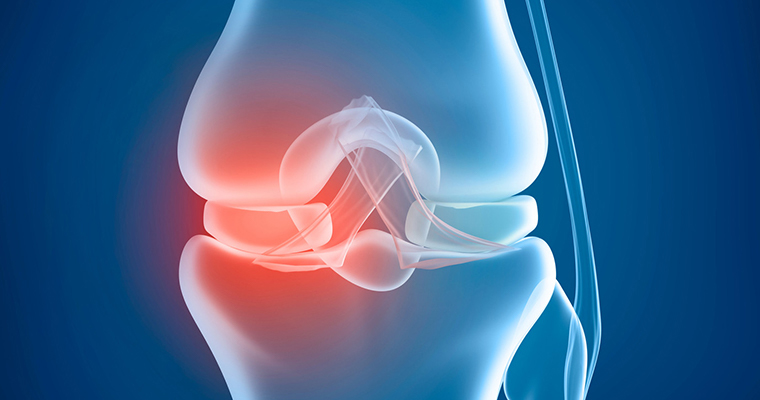

Knee Osteotomy

Knee Osteotomy

High Tibial Osteotomy is most effective for active patients who are 40 to 60 years old. Good candidates have pain on only one side of the knee and no pain under the kneecap. Knee pain should be brought on mostly by activity, as well as standing for a long period of time.